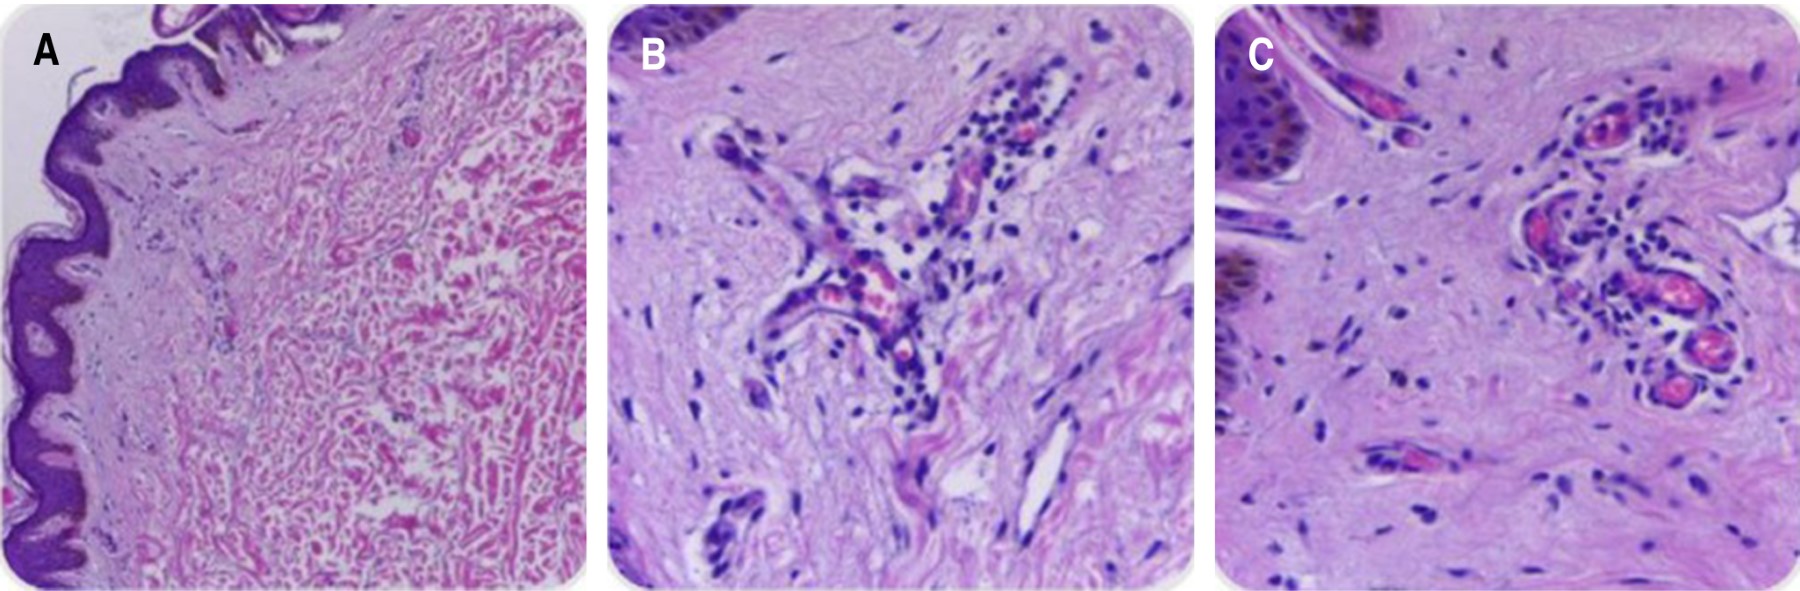

Figure 1

Figure 2

Figure 3